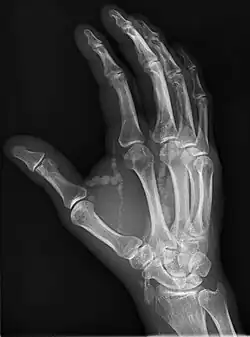

Hand radiograph showing tumoral calcinosis, PA radiograph of the right hand showing tumoral calcinosis-like metastatic calcification in a patient on dialysis. Dialysis alters calcium phosphate product (>70). Idiopathic tumoral calcinosis is autosomal dominant and is not associated with dialysis. Note the premature arterial calcification which is a clue that this is a renal patient. Vascular calcification contributes to an increase in morbidity.

Oblique hand radiograph showing tumoral calcinosis

Oblique radiograph of the right hand demonstrating soft tissue calcification, characteristic of dialysis related metastatic calcification.